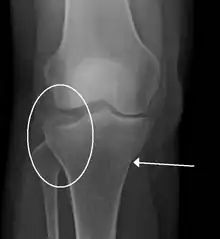

| A severe tibial plateau fracture with an associated fibular head fracture | |

A tibial plateau fracture seen on X-ray